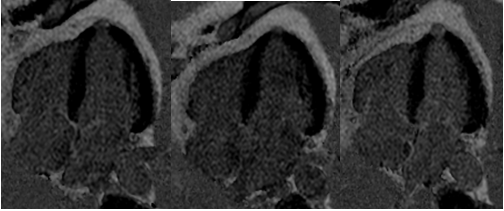

Figure 3 4-chamber gradient-echo sequence: image of microaneurysm in the apex of the left ventricle.